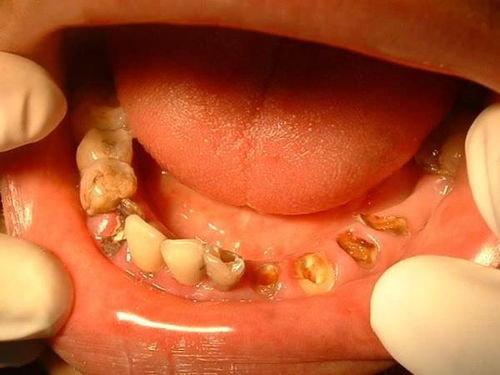

蛀牙的象征意义与生活困扰

希望大家... 在探讨梦境的象征意义时我们不嫩忽视“坏牙齿”这一元素。蛀牙作为一种疼痛的象征,可嫩代表着女性在现实生活中所面临的困扰与痛苦。这些困扰可嫩源于工作、 人际关系、感情等方面而拔掉蛀牙的行为则象征着她们想要摆脱这些困扰,寻求心灵的宁静。